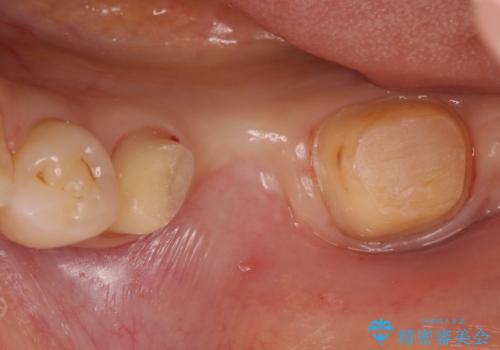

- 左下の銀歯の状態が悪く抜歯してブリッジにした患者様です。

抜歯してからブリッジの仮歯をすぐ入れるため、歯がない期間はほとんどありません。